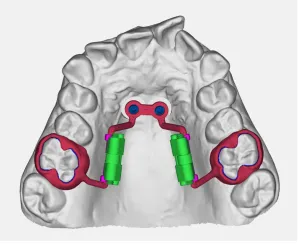

Espansore Ibrido Rimovibile

Dispositivo rimovibile per l'espansione a livello dentale indicato nei pazienti che necessitano successivamente di trattamento con allineatori trasparenti. Ideale per pazienti in crescita che necessitano di flessibilità nel trattamento.